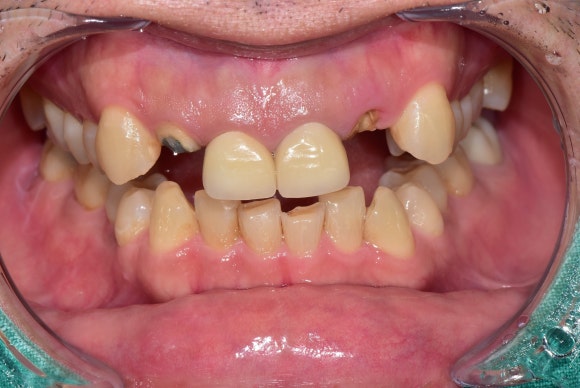

20250310

교정력을 가한지 2주 정도 되었습니다.

새싹이 나오듯이

1~2mm 정도 나오기 시작했습니다.

처음이 어렵지,

한 번 나오기 시작하면 쉽게 나옵니다.